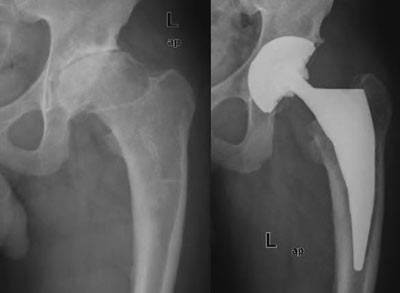

Harris’ hofteskår ble målt preoperativt og postoperativt etter ett år. Gjennomsnittlig skår preoperativt var 49 (spredning 27 – 66) og postoperativt 97 (spredning 76 – 100). Preoperativt var det aktuelle bein kortere (1 – 3 cm) hos 20 pasienter. Postoperativt var beina like lange hos 35 pasienter, hos én pasient var beinet fortsatt 1 cm for kort, og hos én pasient var beinet blitt 1 cm for langt (overkorreksjon). Eksempler på bruk av den individtilpassede hofteprotesen fremgår av figur 6, figur 7 og e-figur 8.

Den elektroniske overføring av data fra CT-opptak på røntgenavdelingen i Arendal til firmaet i Trondheim har fungert godt. Den preoperative dokumentasjonen har vært presis, og de røntgenologiske og kliniske postoperative resultater har vært som ønsket, vurdert ut fra presisjon av collumkutt, korreksjon av beinlengde og funksjon (Harris’ hofteskår). Ingen av pasientene fikk luksasjoner postoperativt eller løsninger senere.